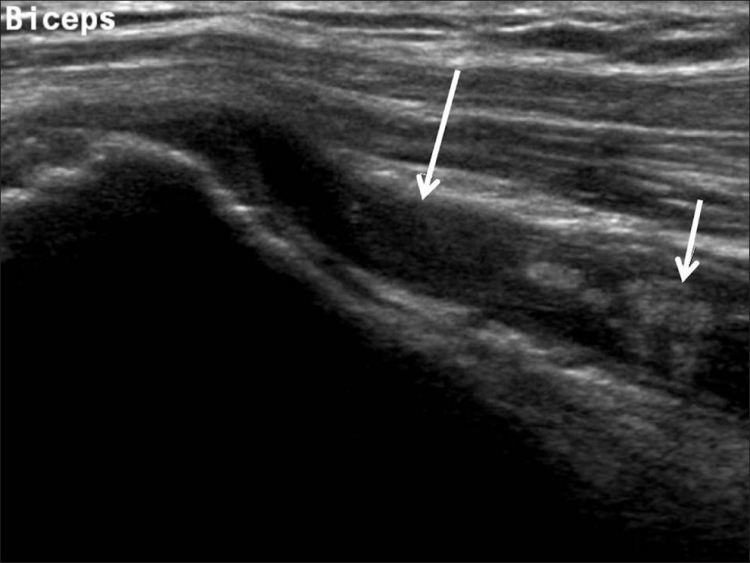

La ecografía del hombro comienza examinando el surco bicipital (BG) y la cabeza larga del tendón del bíceps braquial. El paciente está sentado frente al operador en una posición neutra, su mano colocada con la palma hacia arriba sobre el muslo. Se realiza una imagen de eje corto colocando el transductor sobre la metáfisis humeral proximal perpendicular al húmero. La imagen del eje largo del tendón se obtiene girando el transductor a una posición paralela a la diáfisis humeral [Figura 1]. Luego, se examina el tendón del subescapular. El brazo del paciente se fija sobre el flanco y el antebrazo se abduce en rotación externa. Se realizan vistas de eje largo y corto del tendón [Figura 2]. Los tendones infraespinoso y redondo menor se examinan desde una vista posterior del hombro. El paciente se gira 90°, su mano se coloca sobre el hombro opuesto y el transductor se orienta en el plano axial sobre la cabeza del húmero [Figura 3]. La articulación glenohumeral y la escotadura espinoglenoidea también se examinan en una vista posterior del hombro. El transductor ahora se mueve medial y caudalmente en el plano transversal hasta que se vea el margen posterior de la articulación glenohumeral y luego, más medialmente para mostrar la escotadura espinoglenoidea [Figura 4]. El tendón supraespinoso se escanea en una vista anterior del hombro. El paciente está sentado frente al operador. El brazo del paciente se coloca en una posición posterior, la mano dorsal en el ala ilíaca opuesta o la mano palmar en el ala ilíaca ipsilateral. Se obtienen vistas de eje largo y corto del tendón supraespinoso. Luego se realiza la exploración del manguito de los rotadores durante las maniobras dinámicas. El transductor se coloca sobre el acromion. El brazo del paciente se abduce con el codo flexionado a 90° o/y el brazo se extiende anteriormente [Figura 5]. Finalmente, se escanea la articulación acromioclavicular. La mano del paciente se coloca con la palma hacia arriba sobre el muslo. El transductor se coloca sobre la parte superior del hombro en un plano coronal [Figura 6].

Los desgarros del manguito de los rotadores son la patología más común que se encuentra en los exámenes de ultrasonido del hombro.[7] La incidencia de lágrimas aumenta con la edad. Los desgarros de tendones se pueden clasificar de acuerdo con el grado de falla de la fibra, que van desde desgarros completos [Figura 7], desgarros de espesor total [Figuras 8, 9], desgarros de espesor parcial [Figuras 10-12] y desgarros intrasustancia [Figura 13 ]. Un desgarro agudo suele ir acompañado de derrame articular o bursal [Figura 12]. [7-9] La ausencia de derrame generalmente se relaciona con desgarros crónicos.[9] En un metanálisis sobre la precisión de la resonancia magnética, la artrografía por resonancia magnética y la ecografía en el diagnóstico de desgarros del manguito de los rotadores, la ecografía ofreció una alta sensibilidad y especificidad para la evaluación de los desgarros del manguito de los rotadores de espesor total (92,3 y 94,4 %, respectivamente) con 85,1 % y 92 %, respectivamente para todas las lágrimas.[7] El desgarro de espesor parcial aparece como un defecto o hendidura hipoecogénica en el tendón, afectando solo una parte de su espesor, mientras que un desgarro de espesor total se extiende desde la bolsa hasta la superficie articular del tendón. Un desgarro completo es un desgarro de espesor completo que afecta todo el ancho del tendón. El tendón se retrae medialmente, y la cantidad de retracción depende de la edad del desgarro. En las roturas crónicas, el tendón desaparece por debajo del arco coracoacromial, dejando la cabeza humeral descubierta por el supraespinoso, el denominado signo de la "cabeza desnuda". Los hallazgos de la ecografía incluyen la falta de visualización del tendón y la hernia del músculo deltoides. Los desgarros intrasustancia permanecen localizados en el tendón sin afectar sus márgenes. Los desgarros intrasustancia y de espesor parcial pueden ser difíciles de diferenciar de la tendinopatía focal.